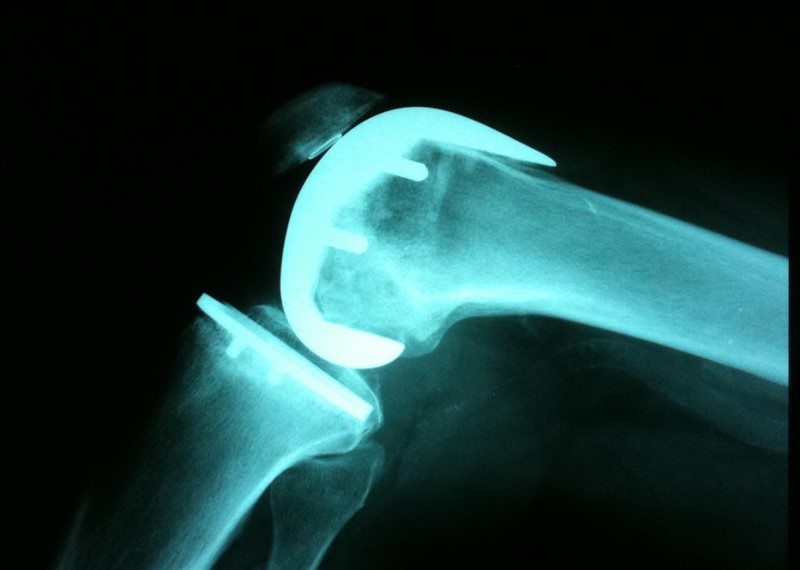

Acupuntura para la artrosis de rodilla

La electroacupuntura se puede utilizar para mejorar el dolor y la función física en adultos con osteoartritis de rodilla. La electroacupuntura parece ser más efectiva que la acupuntura con aguja para los síntomas de la osteoartritis de rodilla, pero ambos tratamientos son más efectivos que la atención estándar. La acupuntura con aguja ofrece alivio del dolor y mejora funcional, pero no consistentemente a niveles clínicamente relevantes. . Am Fam Physician.   agosto 2020

Fisioterapia o corticoides en artrosis de rodilla

Los pacientes asignados a terapia física tuvieron mejor funcionalidad y menos dolor al cabo de un año que los tratados con una aplicación de glucocorticoides intrarticulares. New England Journal of Medicine, 8 de abril de 2020.

Guía de la Fundación del American College of Rheumatology / Arthritis para el manejo de la artrosis de la mano, la cadera y la rodilla de 2019

La Guía americana 2019 sobre artrosis de mano, cadera y rodilla desaconseja el uso de glucosamina, condroitin sulfato, bifosfonatos, metotrexato, hidroxicloroquina, inhibidores del factor de necrosis tumoral (anti FNTa) y los antagonistas de los receptores de interleucina-1 (Anti IL-1), inyecciones intraarticulares de ácido hialurónico, inyecciones de tóxina botulínica, inyecciones de  céulas madre, y  plasma rico en plaquetas entre otras Arthritis Rheumatol. 6 de enero de 2020

Paracetamol para el tratamiento de personas con osteoartritis de cadera o rodilla

Cochrane Database of Systematic Reviews, 25 de febrero de 2019Basada en evidencia de alta calidad, esta revisión confirma que el paracetamol proporciona solo mejoras mínimas en el dolor y la función para las personas con osteoartritis de cadera o rodilla, sin un mayor riesgo de eventos adversos en general. El análisis de subgrupos indica que los efectos sobre el dolor y la función no difieren según la dosis de paracetamol. Debido al pequeño número de eventos, no estamos seguros si el uso de paracetamol aumenta el riesgo de eventos adversos graves, retiros debido a eventos adversos y tasa de pruebas de función hepática anormales.Las guías clínicas actuales recomiendan sistemáticamente el paracetamol como el medicamento analgésico de primera línea para la osteoartritis de cadera o rodilla, dada su baja frecuencia absoluta de daño sustantivo. Sin embargo, nuestros resultados requieren una reconsideración de estas recomendaciones.